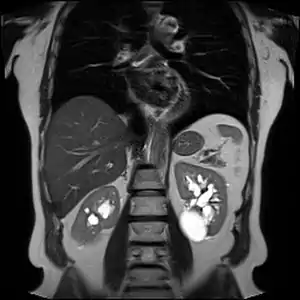

| کیست کلیوی کلیه در سمت چپ (ناحیه hyperintense) که در MRI نشان داده شدهاست. | |

- ام.آر. آی

تصاویر ام.آر. آی نیز مانند سیتیاسکن میتواند وجود کیست و تومور را در کلیه نشان دهد.[1]